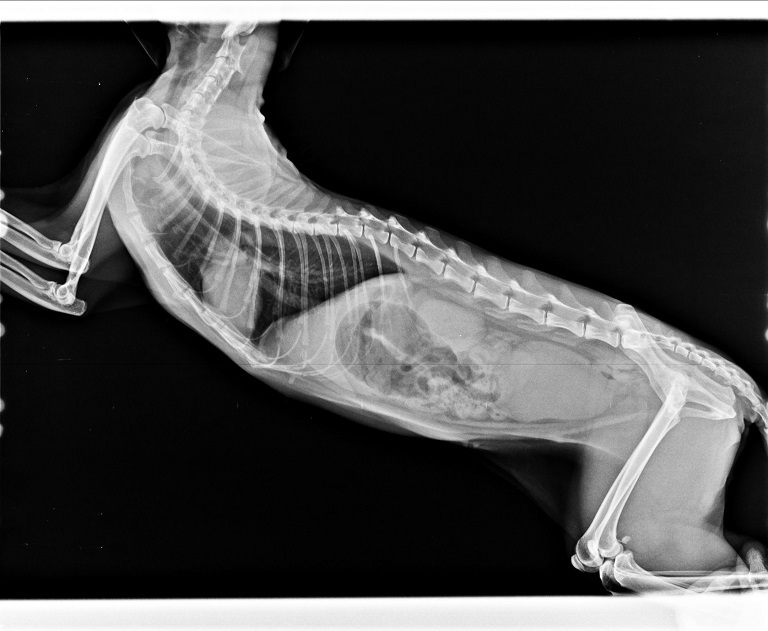

很難想像,小小的身軀承受了多次血液生化檢查、、耳垢檢查、糞檢、X光片、血巴東核酸診斷檢驗、皮下點滴注射、口服抗生素、化痰藥、抗組織胺、食慾促進劑、腸內寄生蟲驅蟲、肝腦錠、消化酵素、消炎眼藥水、耳藥水、噴霧,這些對她來說都是精神上的壓迫,肉體上的折磨,而她總是那個靜靜的、帶點惶恐的樣子躲在角落,承受著一切。